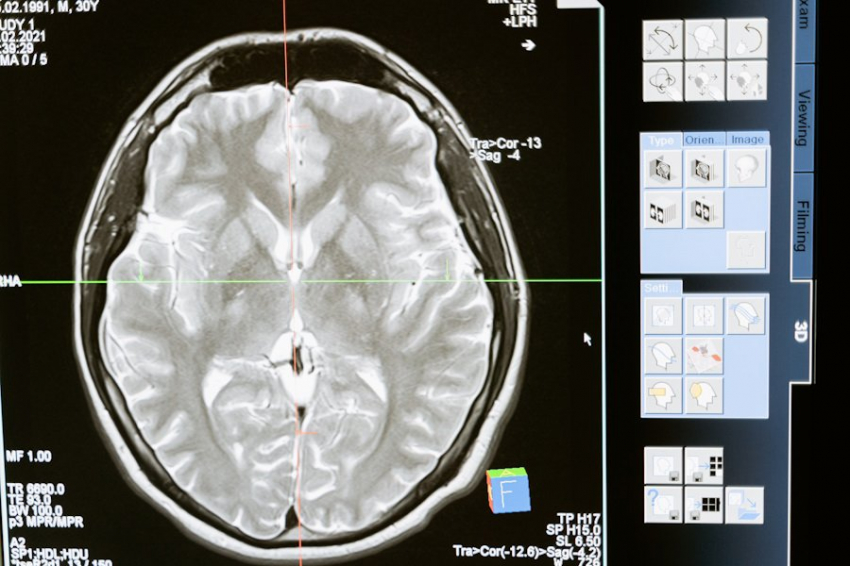

Выяснилось, что редкий дефект гена нарушает работу белков, ответственных за правильное сворачивание других белков — важный процесс, обеспечивающий нормальное функционирование клеток. Эти белки входят в состав молекулярного комплекса TRiC/CCT, который, как оказалось, играет ключевую роль в поддержании нормального развития мозга. Нарушение работы TRiC/CCT влечет за собой неправильное формирование клеток и сбои в работе нервной системы.

Для проверки гипотезы ученые провели эксперименты с круглыми червями C. elegans, гены которых на 50% сходны с человеческими. Мутировавшие черви, несущие дефектный ген, показывали снижение подвижности, что свидетельствовало о проблемах с нервной системой. Исследователи также обнаружили, что из-за дефекта в белке CCT3 нарушается нормальная структура актиновых белков, которые отвечают за форму и движение клеток. В клетках мутировавших червей было зафиксировано аномальное распределение актина, что подтвердило влияние дефекта на формирование клеток и нервную активность.

Дополнительные опыты с рыбками данио-рерио и дрожжами подтвердили, что мутации в гене CCT3 вызывают аналогичные аномалии в развитии мозга и работе сворачивающего механизма белков. Это позволило ученым объединить подобные генетические дефекты в новую категорию редких заболеваний, связанных с комплексом TRiC/CCT.